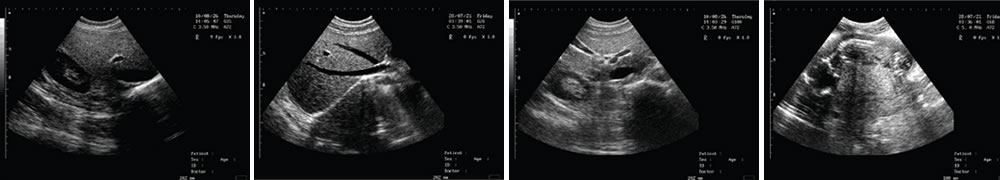

● 顯示模式:B、B/B、B+M、M、4B;

LED高清晰顯示器 一流的數字成像技術